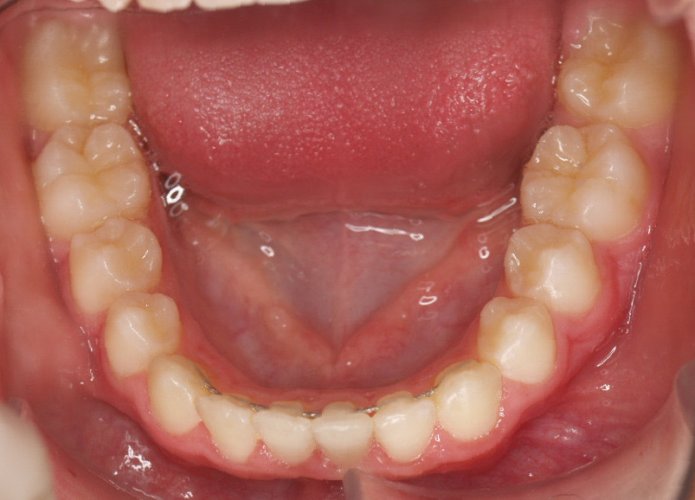

Paciente de 13 años que presenta sonrisa disarmónica.

- Clase I esquelética

- Clase I molar

- DDM +++ anterior

- Sobremordida

Decidimos extraer los 4 primeros premolares.

A los dos años quitamos aparatología fija y la paciente entra en fase de contención encantada con su nueva sonrisa.

Lleva férulas ESSIX a la noche más una contención fija inferior de canino a canino.